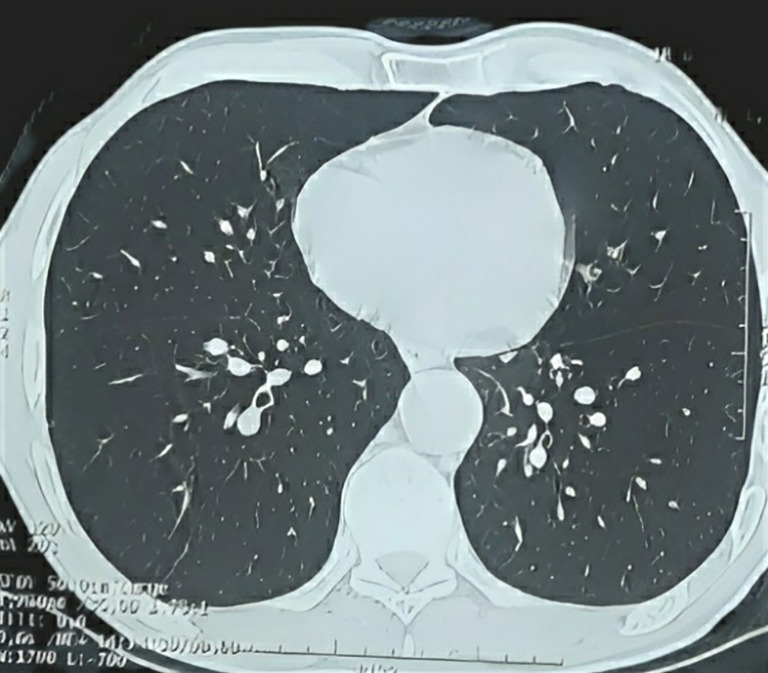

Case description: We present the case of a 64-year-old male patient from Casablanca with no notable medical history who reported right low back pain without accompanying fever and exhibited signs of a deteriorating general condition. Clinical examination revealed tenderness upon palpation of the right flank and a left thyroid nodule. Ultimately, a diagnosis of RPF secondary to prolonged occupational asbestos exposure was established. The patient underwent the insertion of a right JJ stent and received combined corticosteroid therapy.

Abstract Image